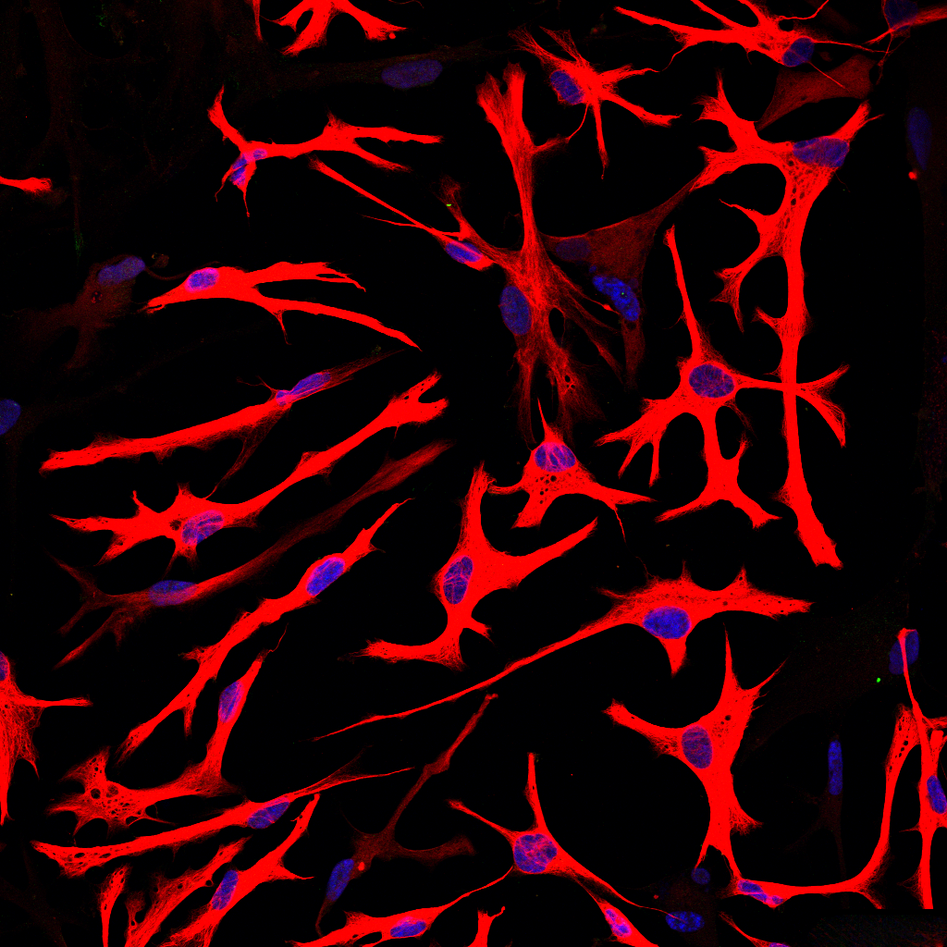

We are using stem-cells transformed from the patient’s own fibroblasts to study the mitochondrial disease caused by POLG mutations. These “induced pluripotent stem cells” (iPSC) offer a unique opportunity to model human disease in a renewable and tissue-specific manner. Thus far we have successfully generated neurones and all glial cell types, cardiomyocytes, and hepatocytes from these iPSCs.

We have established the required competence and facilities for human induced pluripotent stem cell (hiPSC) reprogramming and differentiation, enabling investigation of neuronal cells from patients and healthy controls. Validated iPSCs are differentiated to neural stem cells (NSCs) and regionalized neuronal subtypes, as well as astrocytes/ glial populations. A postdoctoral fellow in our group, Yu Hong, has developed brain organoids and will be using these both to investigate disease mechanisms and to test treatments.

- 2D: neural stem cells, DA neurons, motor neurons, generic neurons, astrocytes, oligodendrocytes and cardiomyocytes.

Modeling diseases using neural stem cells, neurons, astrocytes, and astrocyte-neurons interactions.